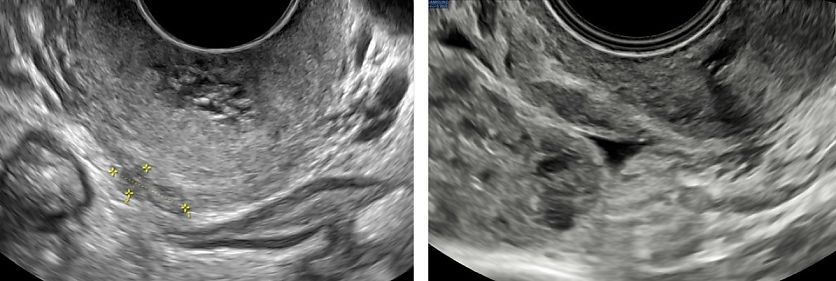

Bladder

The bladder is the most affected organ in cases of DE of the urinary tract. Lesions typically arise from the posterior bladder wall or dome (Figures 9–12), often within the detrusor layer. On TVS, these appear as hypoechoic nodules, sometimes with posterior acoustic shadowing. The lesions can be intramural or transmural, and they may protrude into the bladder lumen (Figures 10–12). Optimal bladder filling is essential for assessing wall integrity and nodule extent. The lesion should be evaluated in three orthogonal planes and its maximal dimensions should be measured, as well as the distance to the ureteral orifices if they are visible.5

Color Doppler can help distinguish between fibrotic and vascularized lesions (Figure 12). When ultrasound findings are ambiguous, or when the nodule is situated cranially, transabdominal ultrasound or MRI may be used as complementary tools.31,3

12

Typical appearance of a bladder endometriotic nodule: hypoechoic, irregular lesion protruding into the bladder wall. On color doppler, it shows moderate vascularization.